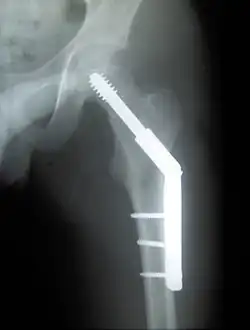

Trochanteric fracture

A trochanteric fracture, below the neck of the femur, has a good chance of healing.

Closed reduction may not be satisfactory and open reduction then becomes necessary.[43] The use of open reduction has been reported as 8-13% among pertrochanteric fractures, and 52% among intertrochanteric fractures.[44] Both intertrochanteric and pertrochanteric fractures may be treated by a dynamic hip screw and plate, or an intramedullary rod.[43]

The fracture typically takes 3–6 months to heal. As it is only common in elderly, removal of the dynamic hip screw is usually not recommended to avoid unnecessary risk of second operation and the increased risk of re-fracture after implant removal. The most common cause for hip fractures in the elderly is osteoporosis; if this is the case, treatment of the osteoporosis can well reduce the risk of further fracture. Only young patients tend to consider having it removed; the implant may function as a stress riser, increasing the risk of a break if another accident occurs.